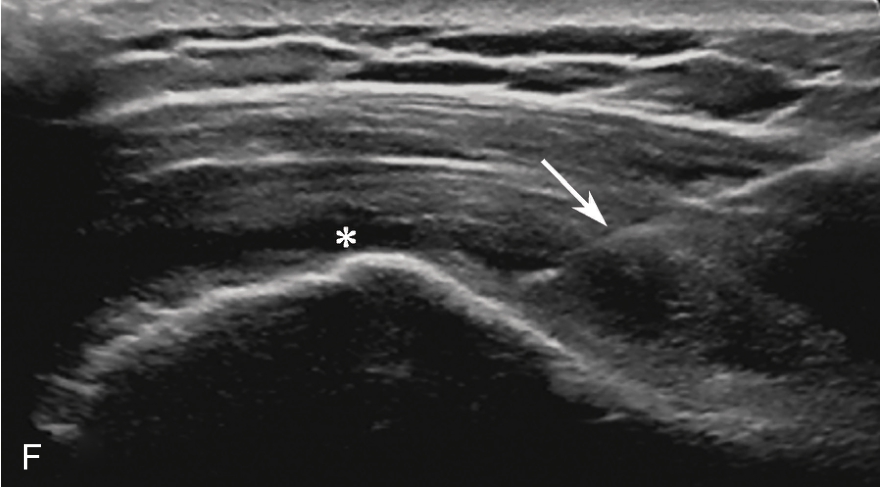

C.彩色多普勒显示囊性团块(星号)内无血流信号;D.超声造影显示囊性团块内呈无增强;E.冈上肌腱完全断裂,关节腔积血(星号);F.超声引导下穿刺液体抽吸及药物注射治疗,箭头示穿刺针